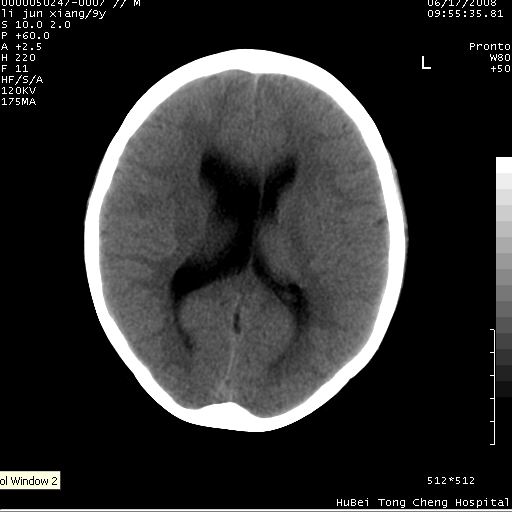

患儿 男,9岁。既往有“脑积水,脑萎缩?”病史(无影像检查资料),现无明显不适。其家长要求ct检查。

颅脑ct轴位平扫(层厚、层距均为10mm),图像如下:

调骨窗:颅骨未见明确异常。

只是双侧脑室不对称,其它未见异常啊